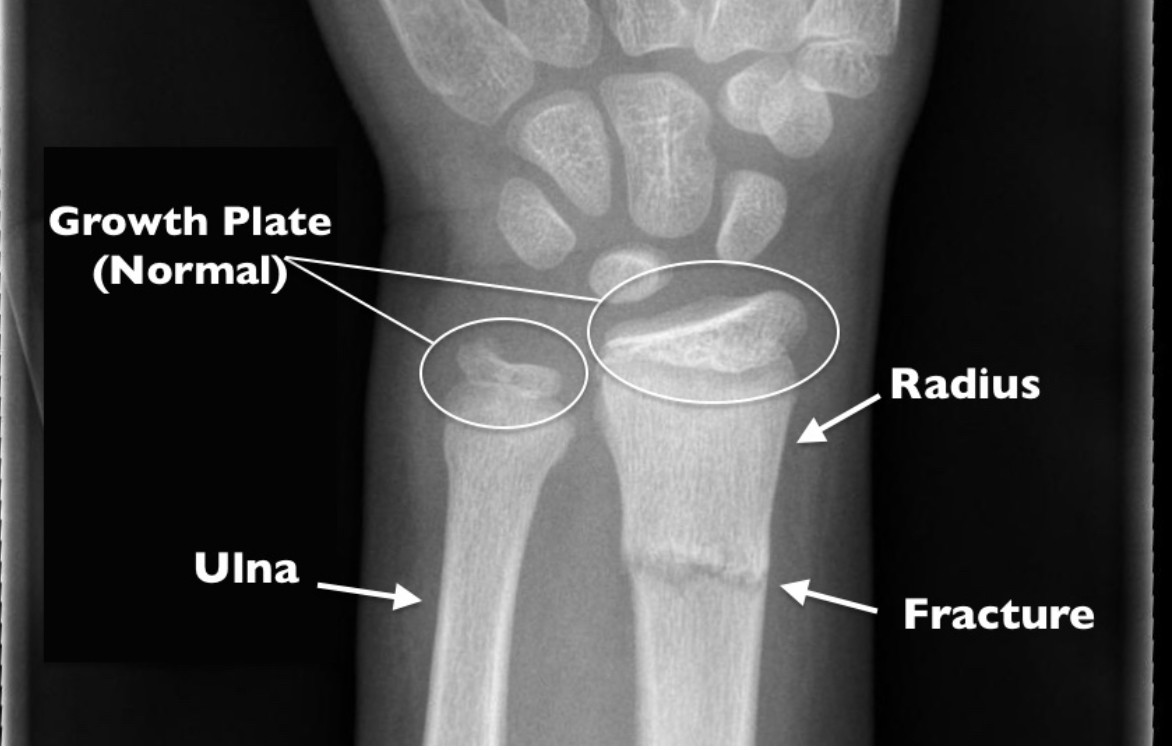

• Rontgen untuk mengevaluasi tulang dan menemukan lokasi fraktur

• CT scan untuk mengevaluasi perubahan struktur secara lebih detil dibandingkan rontgen